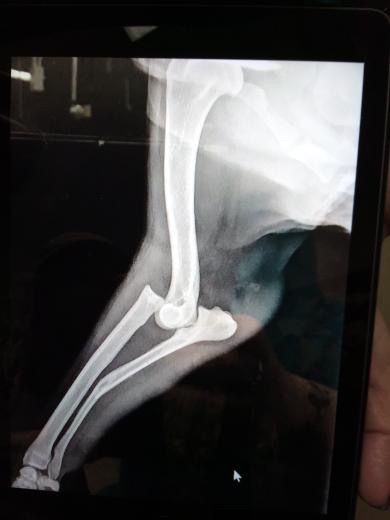

$15,000 is just to raise as much as we can for her surgery. She has a broken back and fractured arms. She needs surgery as soon as possible. She is fighting to live, drinking water, and staying awake. We don’t want to give up on her. Anything that you can give will help, even just kind words and prayers. She helped raise all of us kids and cousins, and we can’t imagine losing her.